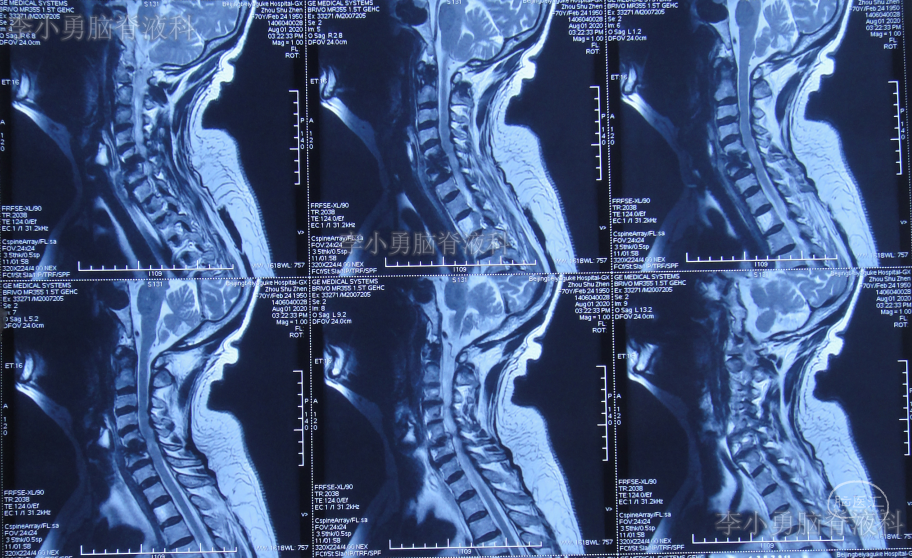

2020年8月4日(即第一次行前路颈5-6椎间盘切除椎间植骨融合内固定术后第114天),再次行颈椎前路颈5、颈6锥体次全切、人工锥体钛板螺钉内固定术,2020年8月5日(即第二次颈椎病术后第1天)复查颈椎平片及颈椎CT示椎管狭窄解除,人工椎体位置良好(图-6、图-7)。

图-6:2020年8月5日颈椎平片

图-7:2020年8月5日颈椎CT